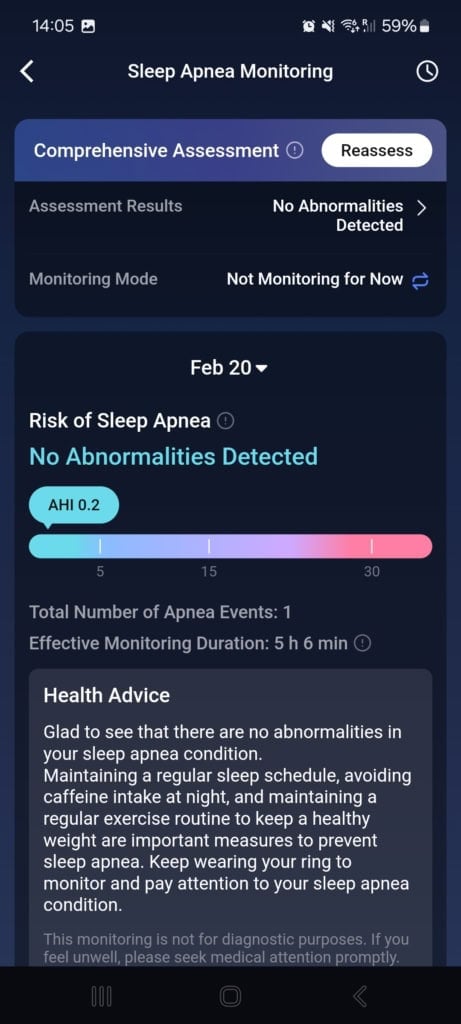

Monitorowanie bezdechu sennego

Smart ring RingConn 2 jako pierwszy wprowadził na rynek monitorowanie obturacyjnego bezdechu sennego. Jest to zaburzenie snu, w którym dochodzi do chwilowego zamknięcia dróg oddechowych. Objawia się znaczną dzienną sennością, głośnym chrapaniem, nocnym budzeniem się czy bólami głowy.

Na podstawie wahań saturacji krwi i tętna w nocy uzyskasz swój wskaźnik bezdechu-hipopnoe (AHI), który oznacza średnią liczbę epizodów z całkowitym zatrzymaniem oddechu i płytkim oddychaniem. Im wyższy wskaźnik, tym poważniejsze może być twoje zaburzenie.

Aby uzyskać kompleksową analizę, smart ring potrzebuje trzech nocy, podczas których wykrywa nieprawidłowości oddechowe. Na podstawie ustalonego wskaźnika dochodzi do zmiany trybu monitorowania. Użytkownicy z niskim lub zerowym wskaźnikiem nie wymagają dalszego monitorowania. Osoby w strefie lekkiego bezdechu mogą zmienić tryb na jedno automatyczne pomiarowanie w celu weryfikacji wyniku. W przypadku wysokiego wskaźnika i podejrzenia średniego do ciężkiego bezdechu dostępne jest codzienne automatyczne monitorowanie.

Po trzech nocach mój wskaźnik wyniósł 0, 0,2 i 0,3 i nie wykryto żadnych nieprawidłowości. Wartość jest bardzo odległa od dolnej granicy lekkiego bezdechu (5,5), więc nie było potrzeby dalszych pomiarów. Ponieważ nie cierpię na obturacyjny bezdech senny, nie pozostaje mi nic innego jak zgodzić się z tą oceną.